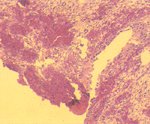

1. 膀胱: 黏膜上皮局部脫落,黏膜層及黏膜下層局部廣泛性出血。 2. 尿道: 黏膜移形上皮脫落,固有層呈淡粉紅均質樣壞死,大量RBC及少量淋巴球浸潤。 3. 腎臟: 多數腎小管上皮細胞發生廣泛性變性、壞死,管腔內有粉紅色滲出物。少數鮑氏囊空隙增大,內含淡粉紅色滲出液。髓質部則出血。 四、 微生物學檢查: 膀胱以血液培養基之培養,經鑑定為 Staphylococcus spp.。 五、 診斷: 山羊尿道結石併發膀胱破裂(Urolithiasis in Goat with Perforation of Urinary Bladder)。